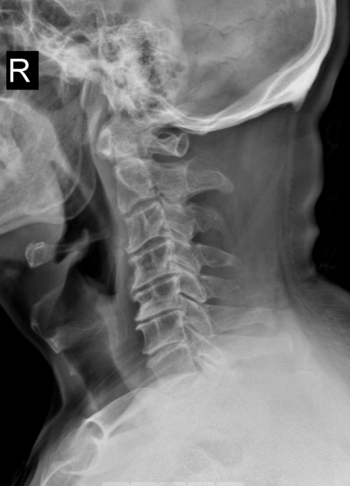

面对这一特殊情况,吴静晔主任没有急于下结论,而是为患者进行了细致全面的检查,最终精准诊断为脊髓型颈椎病。而进一步检查显示,患者存在 C3-T1 多节段狭窄,病情复杂且手术节段较多,这无疑给治疗带来了巨大挑战。

看似确定了治疗方向,真正的难题才刚刚开始。该手术区域解剖结构极其复杂,毗邻人体重要的神经、血管,堪称脊柱外科的「珠峰」。尤其是 C7-T2 椎弓根螺钉置入环节,传统手术极度依赖术中 C 臂透视,却因肩部遮挡,透视、定位极为困难,不仅手术视野受限、置钉难度陡增,螺钉还极易误入椎管,导致术中减压不充分,手术效果完全依赖主刀医生的丰富经验和精湛技术,是业内公认的「硬骨头」手术。